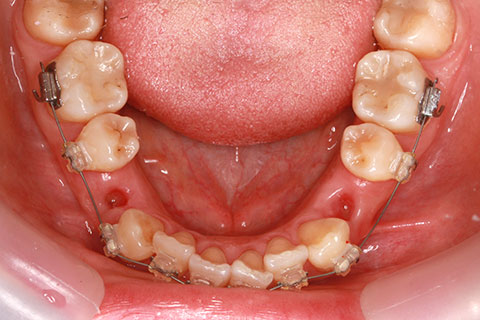

ハーフリンガル矯正3:上の歯のみ舌側矯正で治療(矯正期間24ヶ月)

治療前

治療中(開始直後)

治療中(開始半年後)

治療後

- 年齢・性別

- 25歳女性

- 治療期間

- 2年0ヶ月

- 抜歯

- 上下4番抜歯

- 治療費

- 110万円

- 治療内容

- 施術の副作用(リスク)

- 表側矯正と比較して、力学的な操作性が複雑なため、ボーイングエフェクトを起こしやすい。